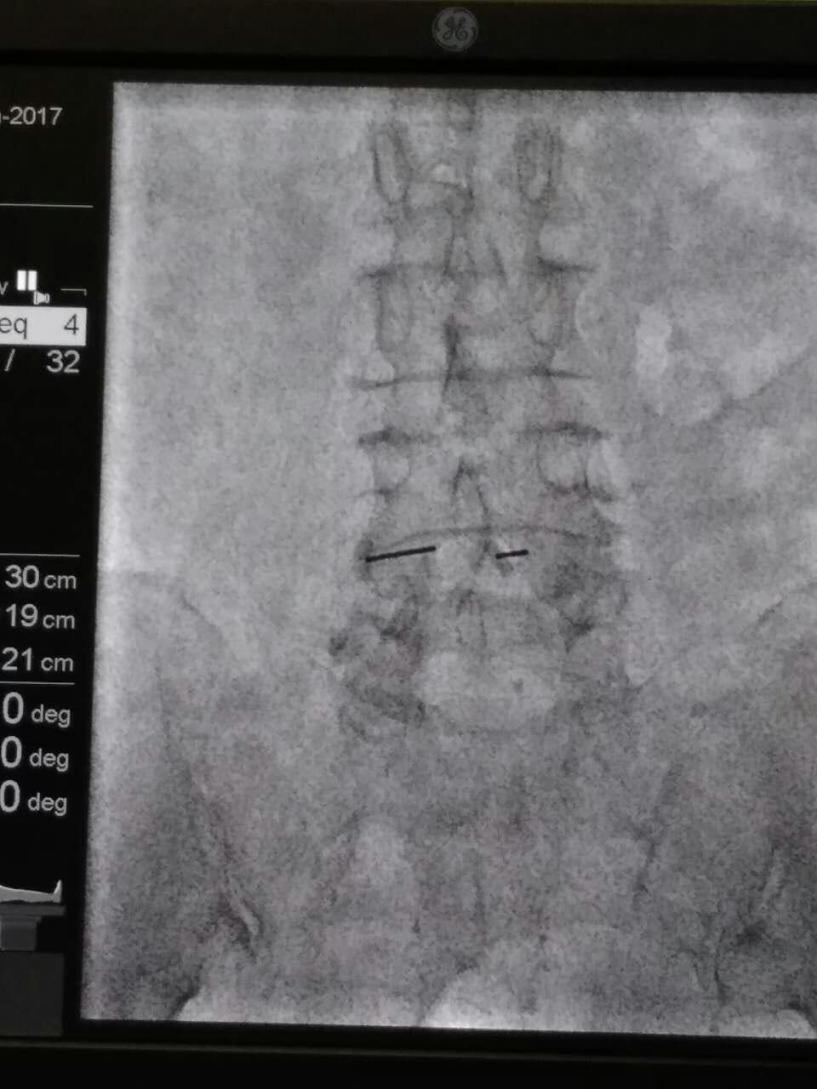

术中,为了定位透照期间为了防避免老人害怕和随时监测,我们团队的杨大夫穿上铅衣陪同老人。由于准备充分,配合给力,手术也异常顺利,半个小时结束。术后的当天中午患者就能和家属坐起来一起吃饭了,家属说这是几个月来的第一次。第二天老人就推着轮椅可以走个不停。前些天我们随访,患者的儿子说:“老人现在每天都下楼两趟溜溜弯。以前,担心老人下不了床;现在,我们担心老人走丢了。”

腰椎管狭窄症,典型的表现就是“间歇性跛行”:走个几十米就出现大腿酸困、麻木和疼痛,强挺着走起来就像瘸了似的,这个时候坐下来歇一会儿,还能走,不过走的会越来越近了。但是这类患者在坐位、骑自行车等会没有什么障碍。我们军工医院疼痛科在查阅文献找寻病因和以往针刀治疗的基础上,进行针刀韧带松解等系列贯序疗法来增大椎管容积、消除椎管内粘连、减小腰背筋膜张力等,从而使腰椎管狭窄症患者的临床症状大大缓解。对于影响生活质量、不愿意或不适合开放椎管减压的患者尤为适合。

对腰椎管狭窄症的关注和影像引导下针刀韧带松解技术的开展,让我们医生多了一种精准微创治疗手段,同时患者也多了一些缓解病痛的希望。